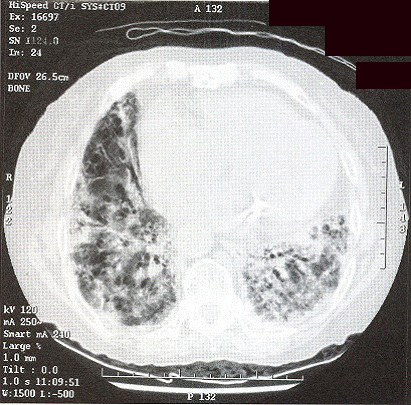

Initially, she was treated as community acquired pneumonia. However her symptom did not improve and she got persistent low-grade fever. CXR showed even more extensive shadow. Bronchoscopy was performed but no endobronchial lesion was found. Transbronchial biopsy was taken from left lingular lobe showed non-specific inflammation. Neither malignant cell nor acid-fast bacilli was found. CT thorax (Fig 3 & 4) was performed which showed widespread ill-defined patchy and nodular opacities and small reactive mediastinal lymph node. CT guided fine-needle aspiration of lung opacity was perfonned but material obtained was insufficient for diagnosis. Her general condition deteriorated despite multiple course of antibiotics treatment. She developed type 1 respiratory failure with oxygen dependency. Open lung biopsy was arranged but was withheld due to poor respiratory reserve. Another session of bronchoscopy was performed. This time the transbronchial biopsy showed evidence of diffuse alveolar damage. Her condition deteriorated further and became bed-ridden. On further questioning, amiodarone has been taken by patient for cardiac problem for few years and was stopped few months prior this admission due to bradycardia. Amiodarone pulmonary toxicity was suspected and oral prednisolone with a dose of Img/kg/day was started.